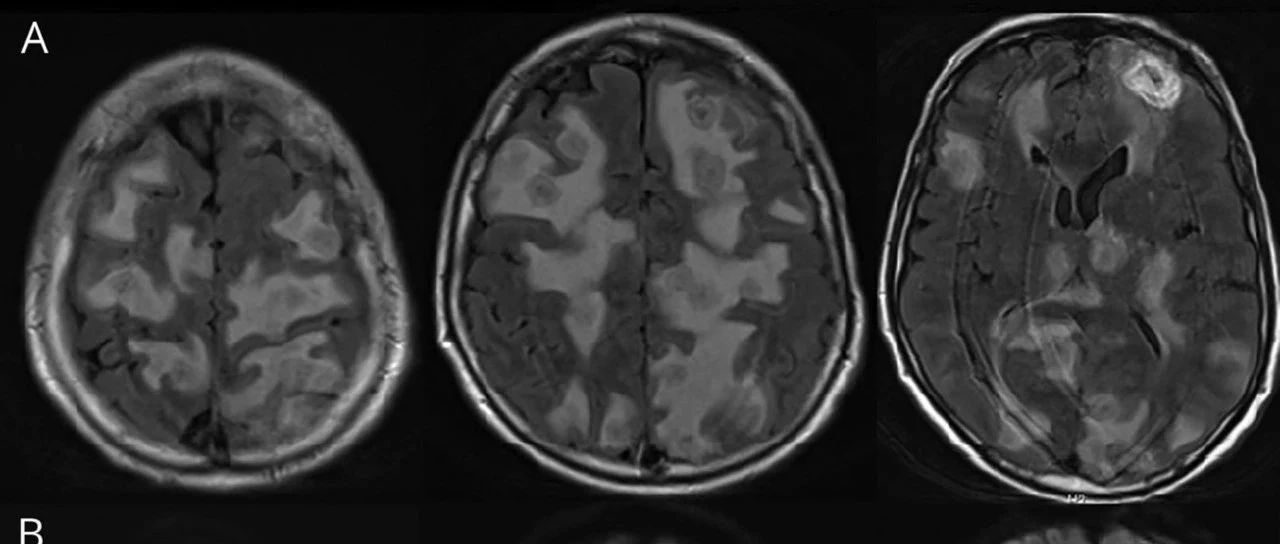

影像挑战:老年男性,进行性头痛和意识模糊(结果公布)

77岁免疫健全男性,表现为进行性头痛和意识模糊。MRI可见大量脓肿。脑脊液化验提示白细胞计数为1250个/mm3(中性粒细胞占65%),微生物培养阴性。二次脑活检,行通用PCR提示为梭杆菌属。最终诊断:脑脓肿。